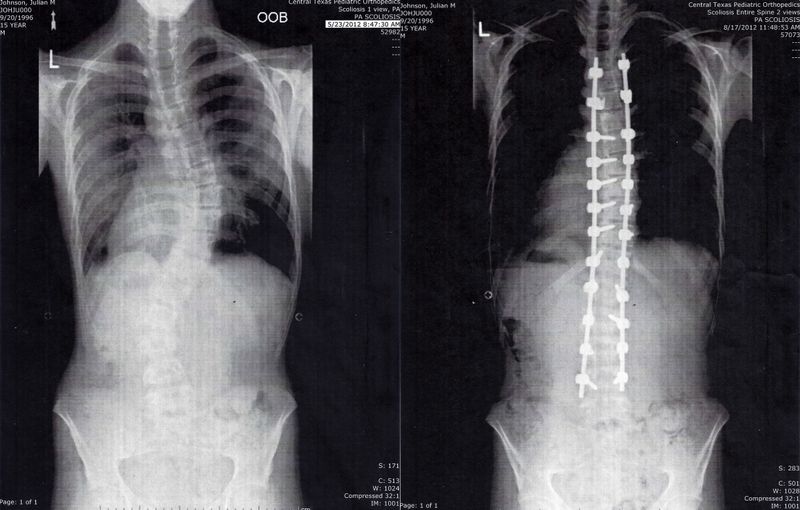

I remember reading about Marfan Syndrome in my high school biology class, the textbook featuring a picture of a skinny boy looking like a deer caught in the headlights. Since getting diagnosed at age five, I’ve been dissatisfied with the cold, clinical imagery surrounding the connective tissue disorder. Even You, Metal Back is an exploration of the intersection of physical pain, mental health, religion, and healing. A self-portrait, if you will, unearthing anxieties around corporality while living with this chronic condition.